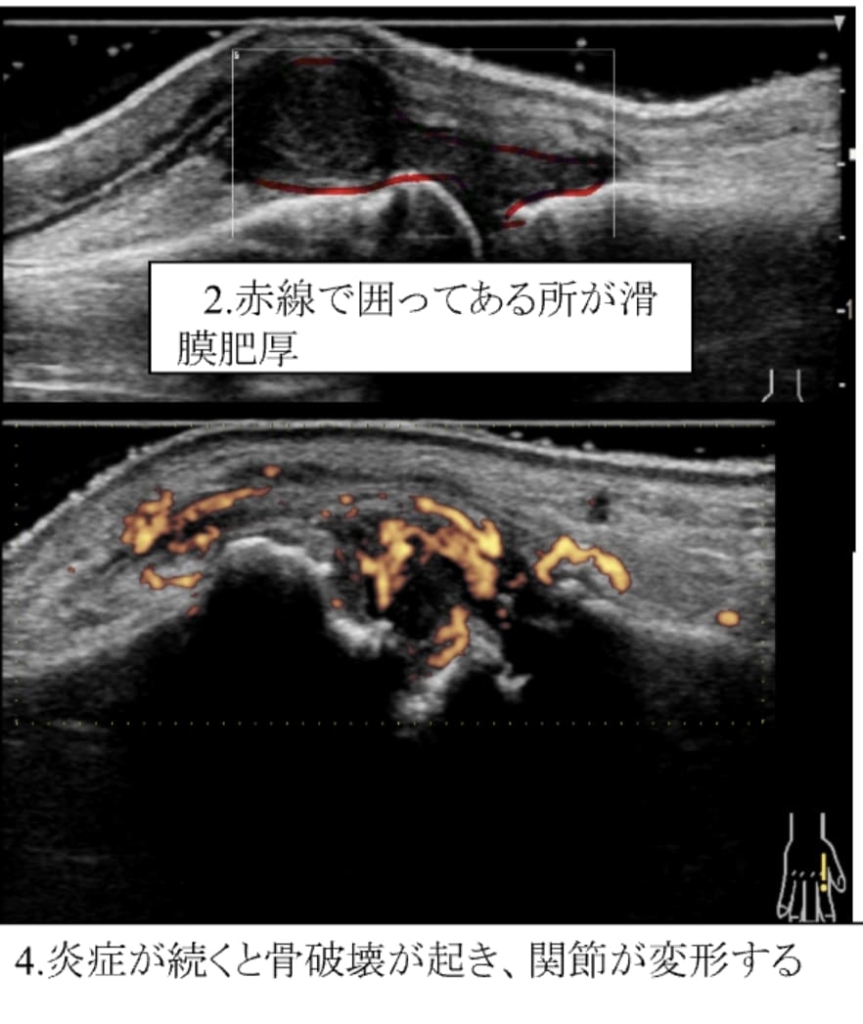

関節リウマチは、関節滑膜が炎症を起こすと厚みを持ち(滑膜肥厚)、滑膜内には異常な血流として示されます(滑膜炎)。これらを「関節エコーガイドライン」に沿って評価し治療に反映しています。

炎症が続くとどうなるの?

同じ関節で炎症が続くと、骨破壊(骨びらん)が起き関節の変形がみられます。また、腱や靭帯で炎症が続くと切れてしまう恐れがあります。

骨破壊によって変形した関節は、元の形には戻すことは困難です。関節の変形や機能低下を防ぐため、年を重ねても使える関節を維持するためにも、定期的な関節エコーは必要だと考えています。(身体メンテナンス大事)。関節リウマチは、採血だけでは診断できません。様々な検査結果から早期診断につなげ、早期治療できるように診療を行っております。